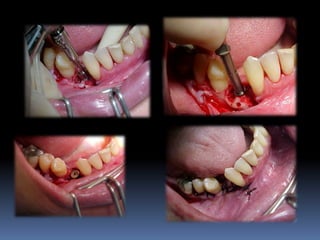

Planejamento em implantodontia

número

Posicionamento

distribuição

tridimensional

Emergência

plataforma

protética

Biomecânica

Distribuições de forças mastigatórias

Extensões distais

Posicionamento tridimensional adequado